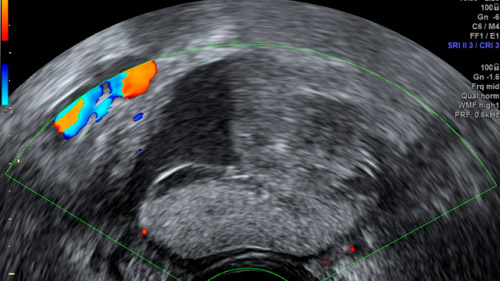

Este tipo de tumor es el más frecuente entre los que no son de origen epitelial y la mayoría se descubren de forma fortuita, durante una revisión ginecológica rutinaria, puesto que no provocan síntomas. Tradicionalmente, el tratamiento indicado había sido la cirugía para extirpar el tumor, pero gracias al estudio se ha observado que, en los casos que no requieren cirugía inmediata, es suficiente con realizar un seguimiento de control mediante la realización de una ecografía transvaginal, a los tres y a los seis meses posteriores al diagnóstico para observar su evolución.

En Dexeus Mujer se considera que las lesiones superiores a 6 centímetros pueden ser más susceptibles de precisar cirugía, aunque pasados los primeros cinco años, el riesgo se reduce, como se ha observado en el estudio. Los autores indican que la ecografía transvaginal es una herramienta eficaz para diagnosticar y hacer el seguimiento de este tipo de tumores.